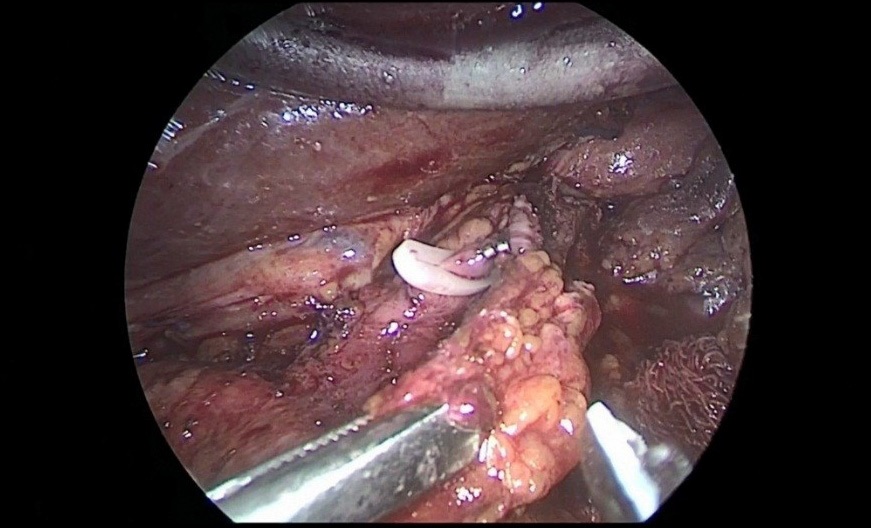

Removed macropreparation: stomach, in the body of the stomach, a tumor with decay elements, 4 X 4 cm in size, with undermined and infiltrated edges (Figure 13a,b). Histological conclusion: Adenocarcinoma G-2 (Figure 14).

Figure 13a,b: Macro preparation: in the body of the stomach there is a tumor measuring 4 X 4 cm.